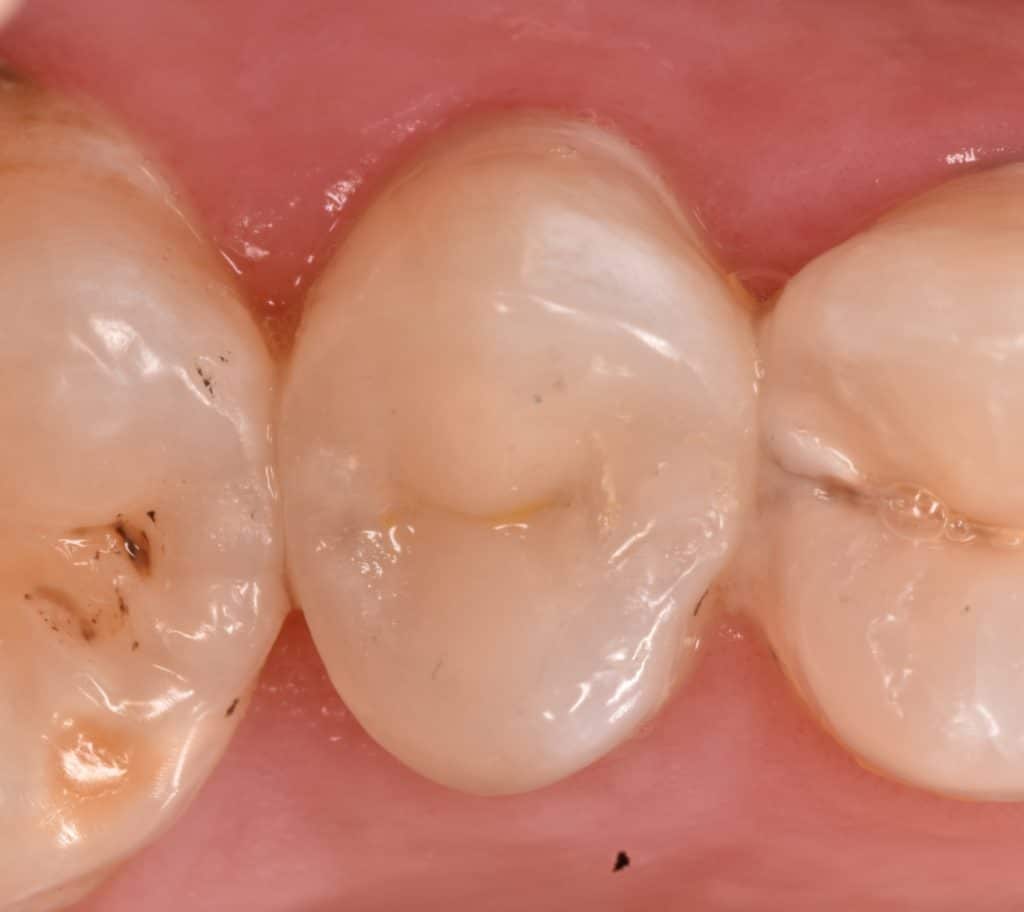

One week later

Look to the gingival healing

Acceptable marginal fitness

14 months follow-up